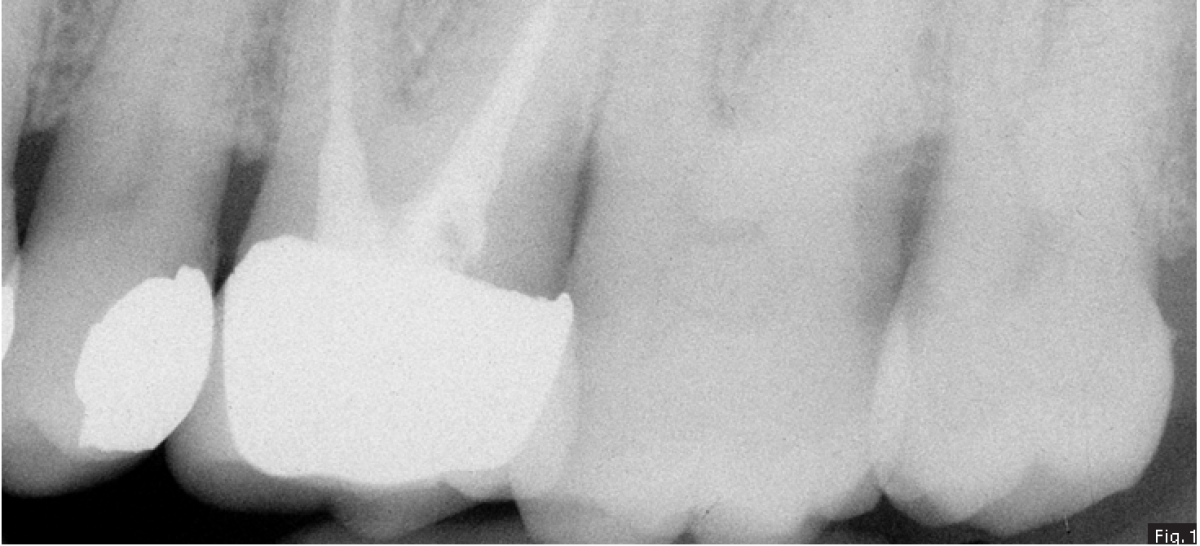

A 62 years old patient was referred to our clinic for endodontic retreatment: the patient reported swelling to the upper left part of the gum. The radiographic examination showed the presence of an existing endodontic therapy and of periapical radiolucencies (Fig. 1). Since the existing therapy could be improved, we decided to retreat the tooth passing through the existing crown. After positioning the rubber dam (Fig. 2), the existing composite filling in the centre of the crown was removed by using a diamond-coated bur driven by a high-speed handpiece. In this way, the access cavity was executed and refined in order to see the pulp chamber(Fig. 3). The existing root canal filling was removed thanks to the use of rotary instruments specifically designed for retreatment, then ultrasonic tips were used to remove the remnants of the pull chamber floor. The chamber was filled with 5 % sodium hypochlorite (Fig. 4) and the MB2 canal, that had not been shaped-cleaned-filled during the initial treatment, was found and it underwent the standard protocol for shaping.

Considering the presence of an endodontic lesion and swelling, a lot of time was dedicated to decontamination of the root canal system (Fig. 5) (18). The device chosen to deliver the irrigating solution right to the working length was IrriFlex (Produits Dentaires SA, Switzerland) (Fig. 6) because, thanks to its flexibility, it was able to deliver the irrigant to the apical third of each root, without any effort, without stopping in case of curvatures. The irrigant was then activated by means of ultrasonic inserts (19) according to the indications given by Tonini et al. (12). After ensuring that the root canals were dry, they were filled according to the warm gutta percha compaction technique (Fig. 8-10). After that, the access cavity was filled by means of a direct composite restoration (Fig. 11) and a post operative x-ray was taken in order to check the final result (Fig. 12).